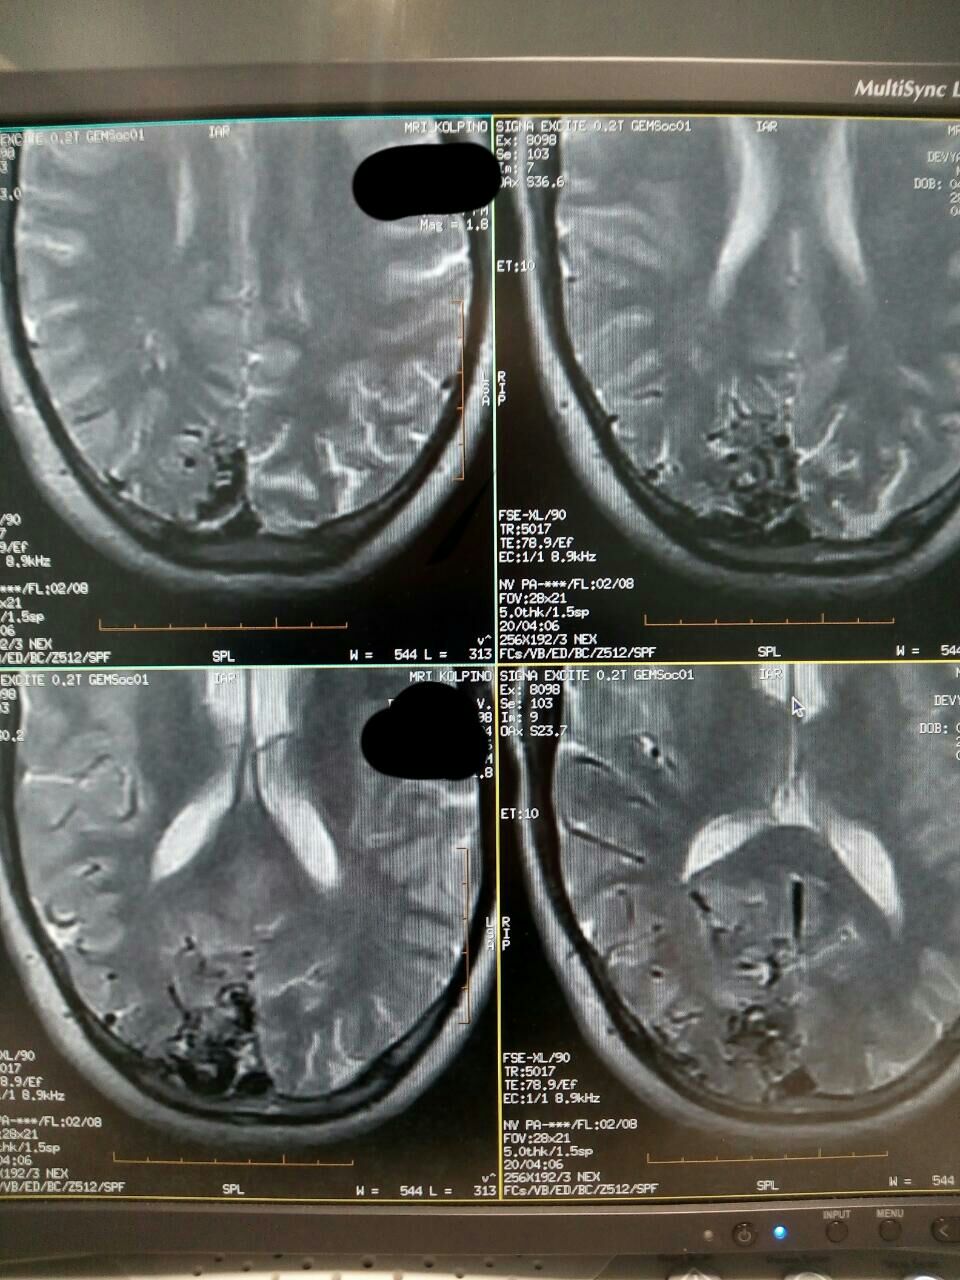

Что тут?

АВМ